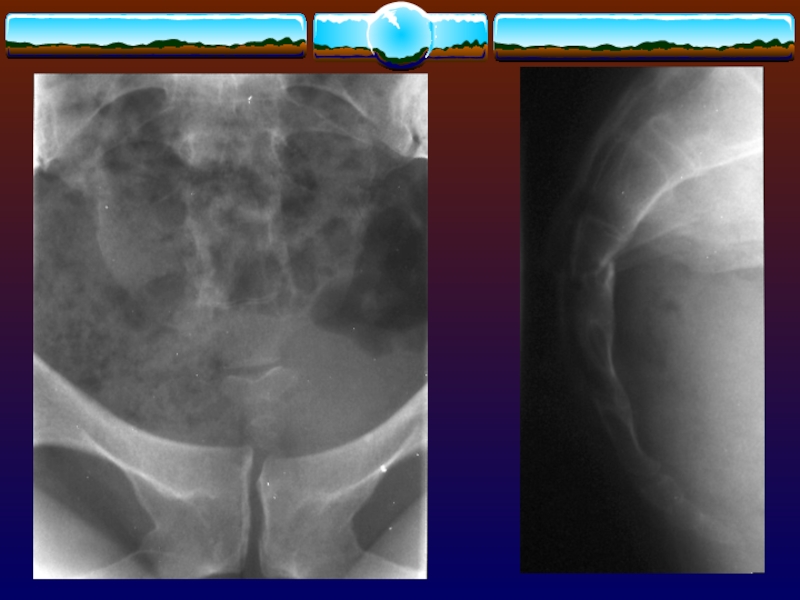

Слайд 103Восходящая уретрография

при выявлении признаков повреждения мочеиспускательного канала и переломах

с расхождением лобкового симфиза

Восходящая уретрография при выявлении признаков повреждения мочеиспускательного канала и переломах с расхождением лобкового симфиза

Слайд 104Цистография

при закрытой травме живота с наличием макрогематурии

при тяжелом

переломе таза

Цистография при закрытой травме живота с наличием макрогематурии при тяжелом переломе таза